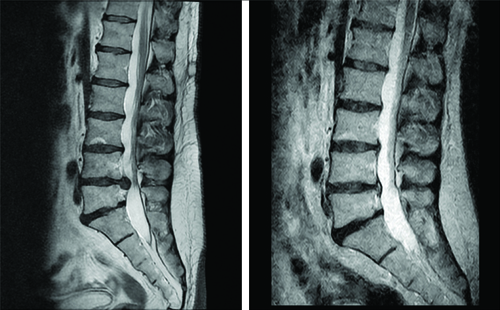

To provide a comprehensive understanding of the changes attained during the treatment program, MRI images of patient one are depicted in both [Table/Fig-6,7]. The improvement achieved is evident from both sagittal and transverse plane images. However, for the sake of quantitative evaluation, only the transverse images were processed. The obtained quantitative data are illustrated through box plot graphs in [Table/Fig-8]. These graphs depict the changes resulting from the treatment, showing a decrease in the AP length and area of the herniation, alongside an increase in the canal indicators. Of particular significance is the observed change in the HI parameter, which provides a comprehensive assessment of the achieved improvements.

Example illustrating the comparison of a sagittal T2-weighted MRI image obtained during the initial visit (left) with that acquired after the completion of the treatment program (right).